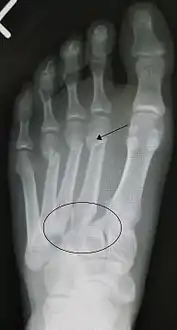

إصابة ليسفرانك (بالإنجليزية: Lisfranc injury) هي إصابة تحدث في القدم، حيث يحدث إزاحة واحد أو أثنان من عظام مشط القدم عن الرصغ.[1]